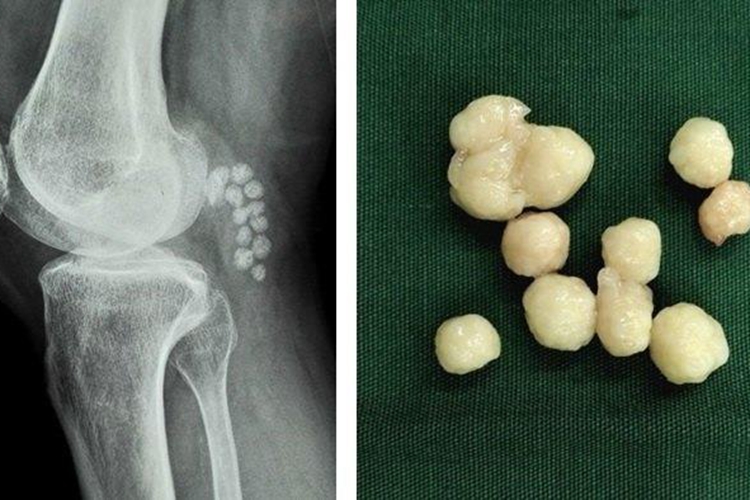

膝关节游离体是一种常见的膝关节病,为关节内与主骨分离后四处移动的小骨块。

膝关节游离体可引起膝关节疼痛,可突然出现交锁现象、膝关节不能屈伸等症状。

摘除关节内游离体,首选为关节镜下手术,对带关节面的骨软骨碎片尽可能复位固定,也可切开关节取出。